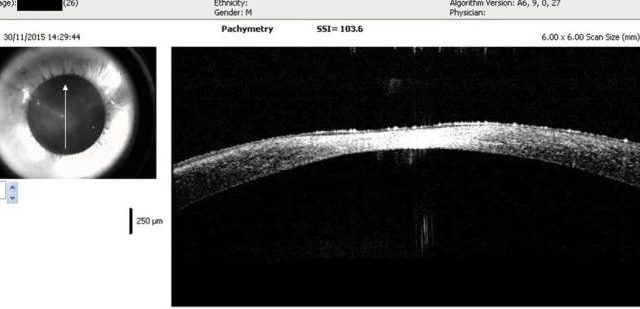

今日分享 发表于1天前屈光说 查看:16661回复:6120 圆锥角膜 圆锥角膜是角膜锥形突起的一种角膜疾病。圆锥角膜病确切病因不清,可能为多因素所致,如遗传因素、内分泌因素等。目前大量临床数据证明过敏性因素和不当的揉眼在圆...